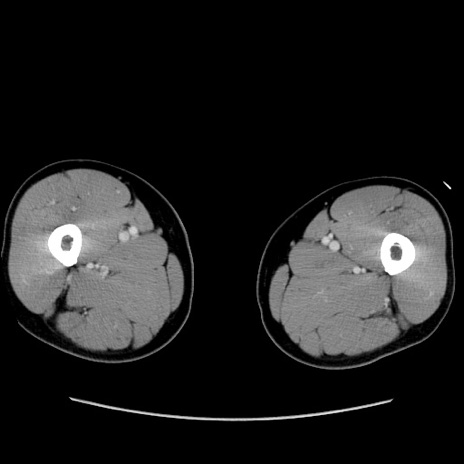

【症例】60歳代 男性

【主訴】右鼠径部膨隆

【現病歴】1年程前より右鼠径部膨隆あり。自己にて還納可能だったため放置していた。3時間前より右鼠径部の脱出を認め、還納困難となり受診。

【既往歴】高血圧

【身体所見】右鼠径部に小児頭大の膨隆あり。弾性硬であり、用手還納は困難。左鼠径部にも膨隆を認める。脱出はなし。